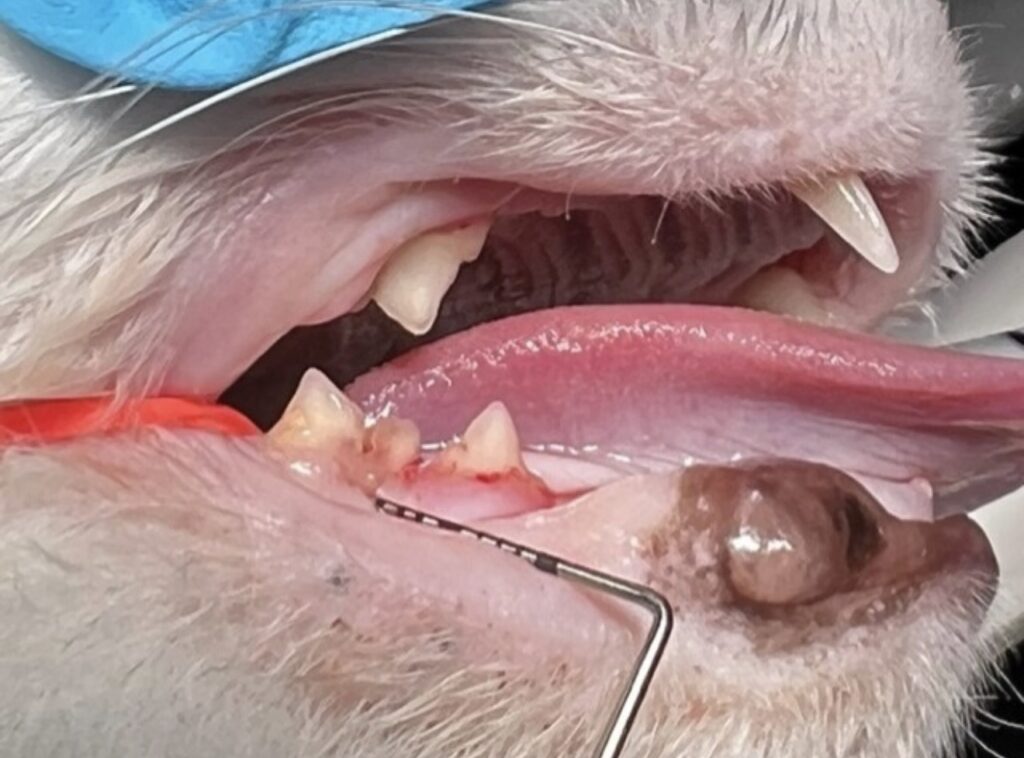

Let me start by saying this: I don’t “vet my own pets.” I intentionally rely on my colleagues to care for them so I can focus on being their mom, not their doctor. It removes the medical stress and allows me to see them simply as my family members. Once Lola was safely under anesthesia, we were finally able to take a thorough look at her mouth. That’s when I learned something that truly surprised me. She had feline resorptive lesions, also known as tooth resorption. In her case, there was a small hole leading into the tooth that had been completely hidden by tartar. It was not visible until after the teeth were cleaned, and it is something I never would have seen during a routine ‘awake’ exam.

Dental x-rays confirmed the diagnosis of tooth resorption, and this step is absolutely critical. Feline resorptive lesions typically begin below the gumline, where we cannot see them with the naked eye. Even teeth that look relatively normal on the surface can be severely affected underneath. Without x-rays, we are only seeing the tip of the iceberg.